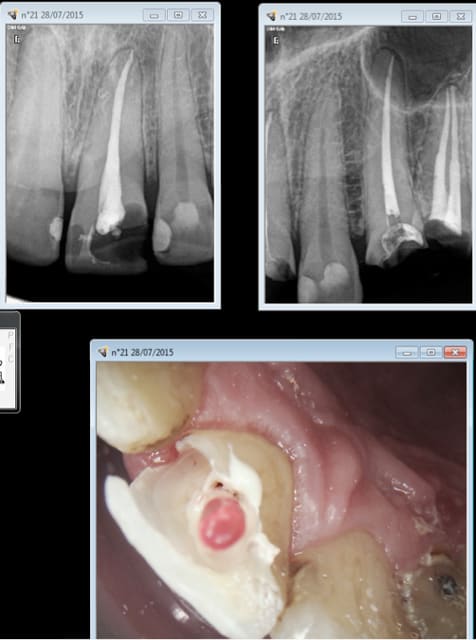

Capture d e cran 2015 07 29 08.31 - Eugenol